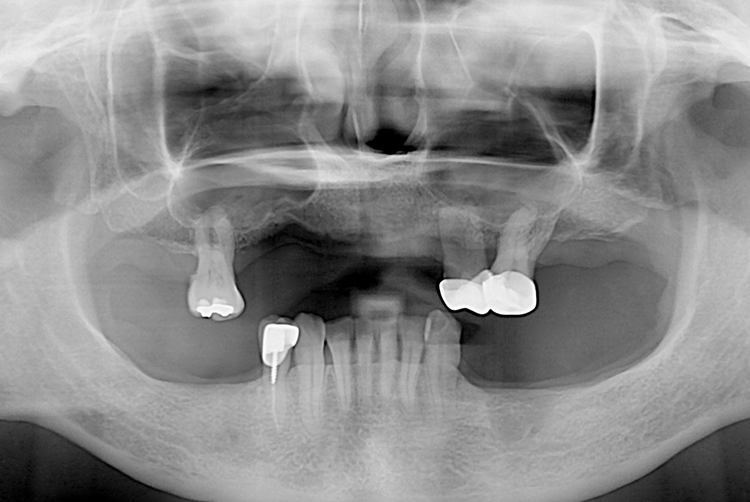

[임플란트] 임플란트

치료전 : 2018-11-02

세종치과는 많은 환자와 다양한 케이스를 바탕으로 항상 편안한 임플란트 수술을 제공하고자 노력하고,

오래동안 튼튼히 쓸 수 있는 임플란트 수술을 가장 큰 목표로 삼고 있습니다